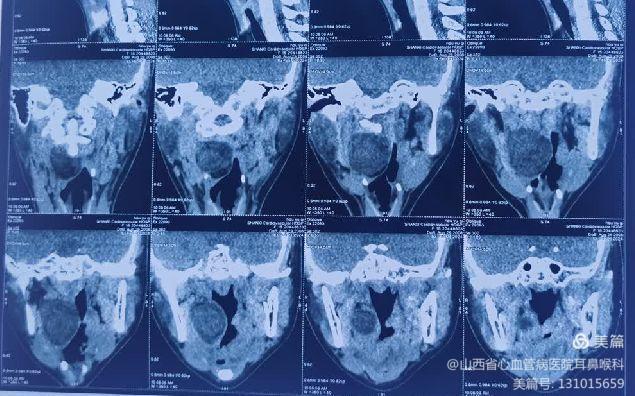

患儿就诊时,自觉偶有憋气及咽痛。张浩杰主任第一时间接诊,经过仔细查体、喉镜和颈部影像学CT与MRI检查后,发现患儿咽腔明显受压,口咽部椎前间隙巨大肿瘤。